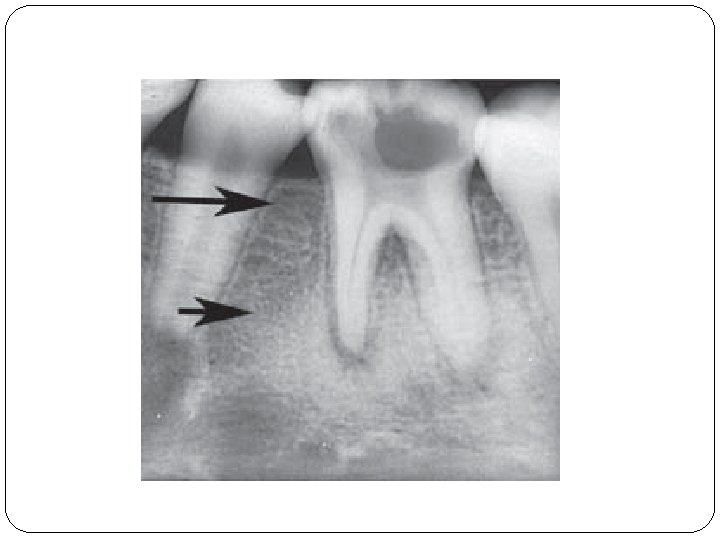

II/E Parodontitis apicalis chronica ossificans �Knochenvedünnüng in der Parodontium �Symptome: keine Beschwerde (Patienten sind oft <20 Jahre alt) �Röntgen: Sklerosis